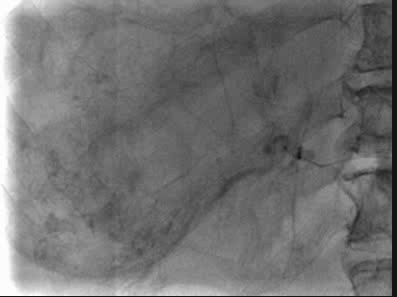

第二次D-TACE手术过程

于2020-9-24行D-TACE,术中造影发现肿瘤染色明显,较前缩小,再分别超选至肿瘤供血动脉,予表柔比星80mg+聚乙烯醇栓塞微球(蓝色型,100-300um)、2支无色型(300-500um),1支无色型(500-700um)栓塞肿瘤供血动脉,直到栓塞至肿瘤血管血流停滞。